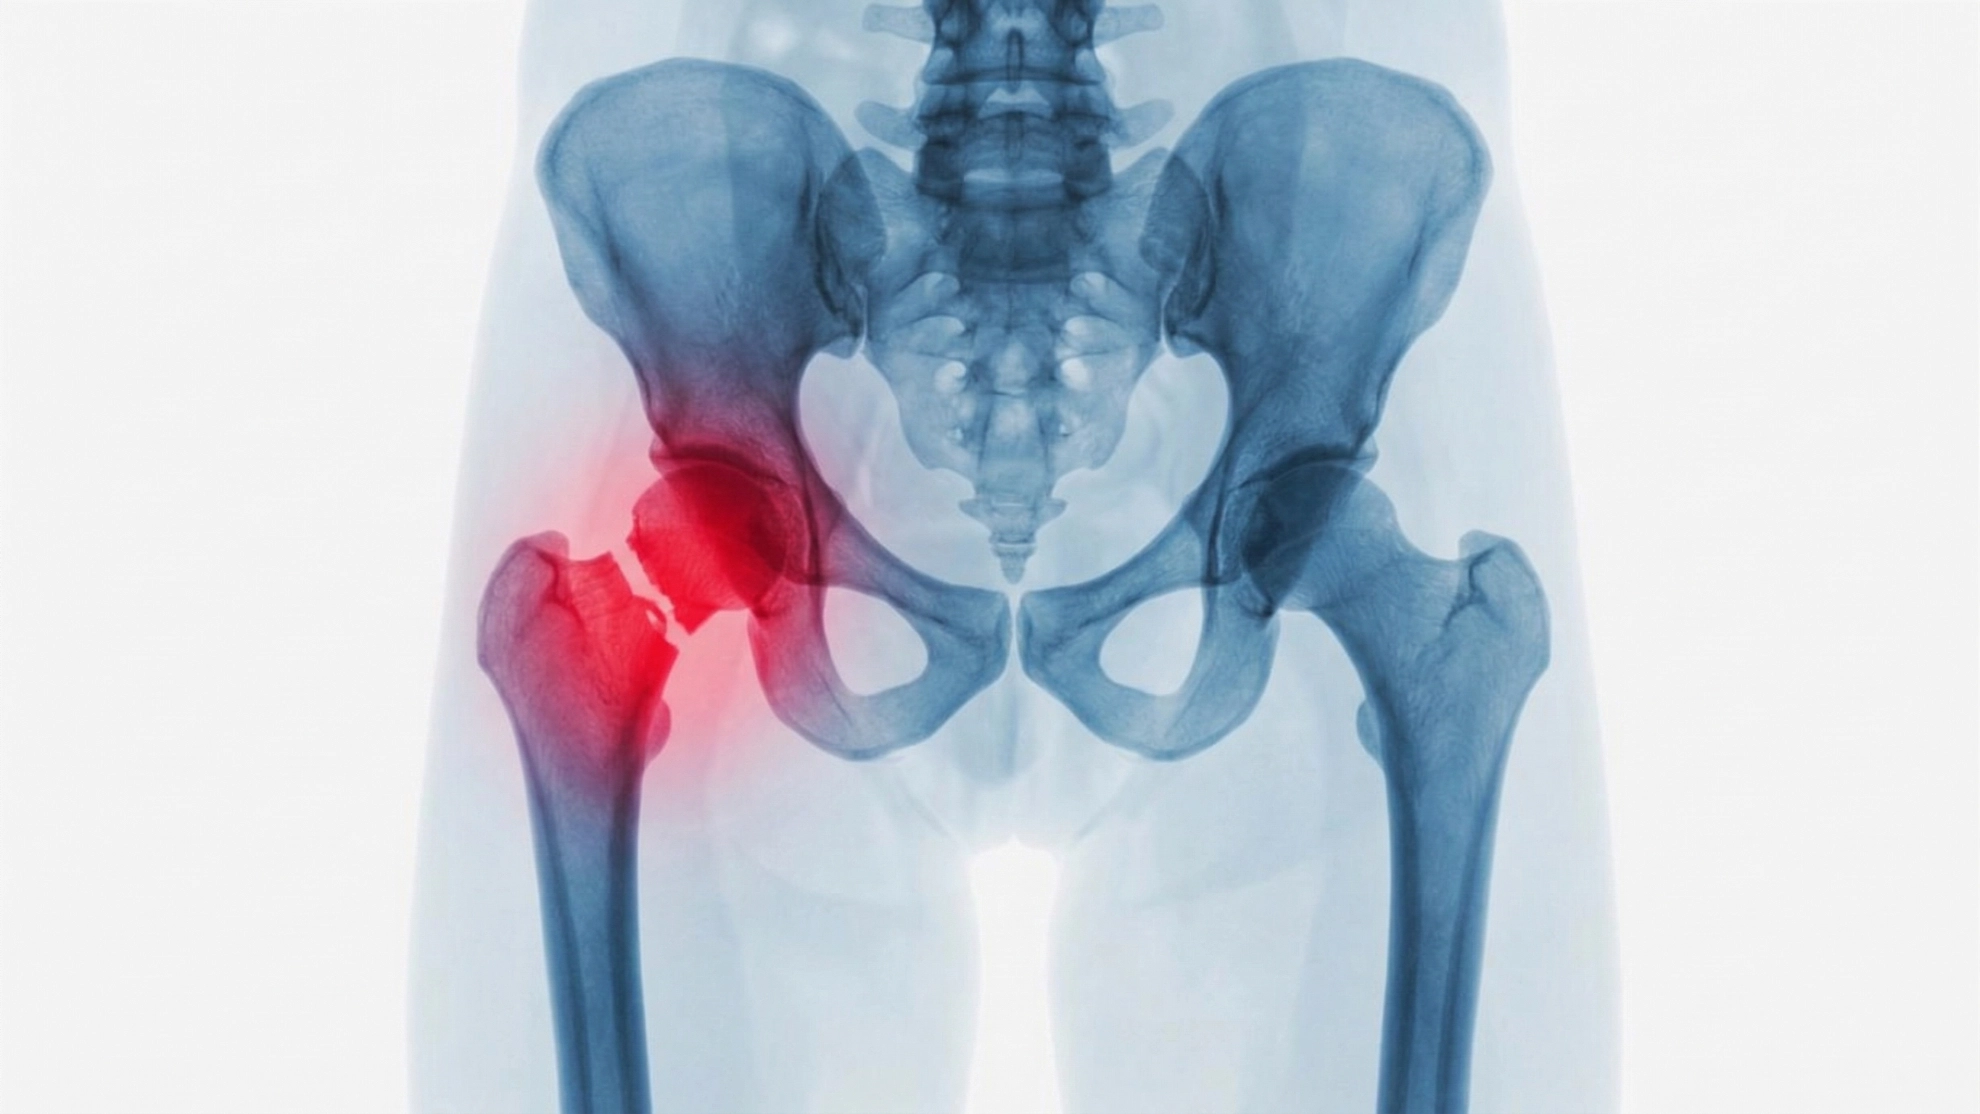

- Hip fractures requiring replacement surgery

- Mortality events following fractures and surgical complications

In fact, for many older adults, a fall is the beginning of a rapid decline in health and quality of life.